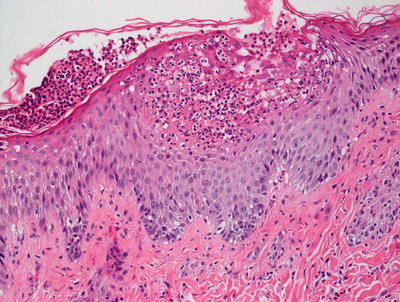

3.5.2 Histology

AGEP is uncommon in children, but when it occurs, shows the same histologic changes as have been reported in adults [35]. Subcorneal pustules comprised of neutrophils are present within a slightly spongiotic epidermis (Fig. 3.12). Parakeratosis is infrequent, except in older lesions. The granular layer persists and acanthosis is not a common finding. Within the dermis, there is a mixed inflammatory infiltrate that consists of neutrophils, eosinophils, and histiocytes [36] (Fig. 3.13).

Fig. 3.13

In addition to the neutrophilic abscesses in the epidermis, AGEP has neutrophils and eosinophils within the dermal infiltrate